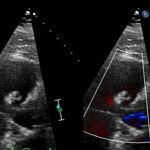

Endovascular coil embolization continues to become a more frequent modality of addressing hemorrhage and bleeding in patients. Migration refers to the coil unraveling or moving from the original embolization site. Migration of a coil is a known complication which can lead to serious consequences based on where the coil migrates. Despite increasing efforts to improve safety and technique, the risk of migration remains. We present a case of an embolization coil that migrated to the right ventricle, which was incidentally found roughly 2 months after undergoing an interventional radiology procedure for gastric variceal bleeding. The patient presented to the emergency department with dyspnea and abdominal pain. Unique images were obtained during his visit and in subsequent follow-up. As use of vascular embolization coils continues to become more commonplace, understanding the risks and complications of these procedures remains an important aspect of providing care for patients once they have left the interventional radiology suite. Coil migration should be a differential to consider in patients who present to the emergency department with signs or symptoms of arrhythmia or pulmonary embolism who have undergone a coil embolization procedure.